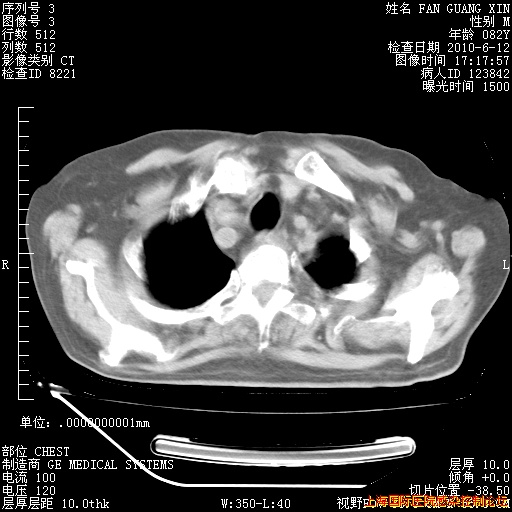

6月12日纵膈窗

回复